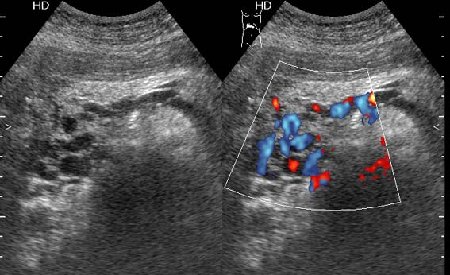

Тромбоз верхней брыжеечной вены

Женщина средних лет, клинический диагноз при поступлении - хронический панкреатит

1.Тромбоз селезеночной вены?

2. Тромбоз вен портальной системы?

Ответ принимается.Инга писал(а):1.Тромбоз селезеночной вены?

Но хочу уточнить - тромбоз какой вены приводит к такому типичному изменению головки панкреас?

Я думаю, что все-таки тромбоз селезеночной вены

Верхней брыжеечной

Да, действительно, формирование варикоза в области головки панкреас характерно для тромбоза верхней брыжеечной вены.Брехт писал(а):Верхней брыжеечной

Ургентность здесь относительная, это неострый тромбоз - для развития коллатералей необходимо время. В хирургической клинике при хроническом панкреатите мы нередко видим тромбозы воротной вены, селезеностой вены. Но тромбоз ВБВ встречается нечасто и заподозрить его можно по "гроздьям" варикозов в области головки панкреас. На пилетромбоз обычно указвают "гроздья" варикозов в воротах печени.besliu писал(а):Спасибо за случай,впервые вижу такую патологию,ургентность в поликлинике не так уж частая![]()